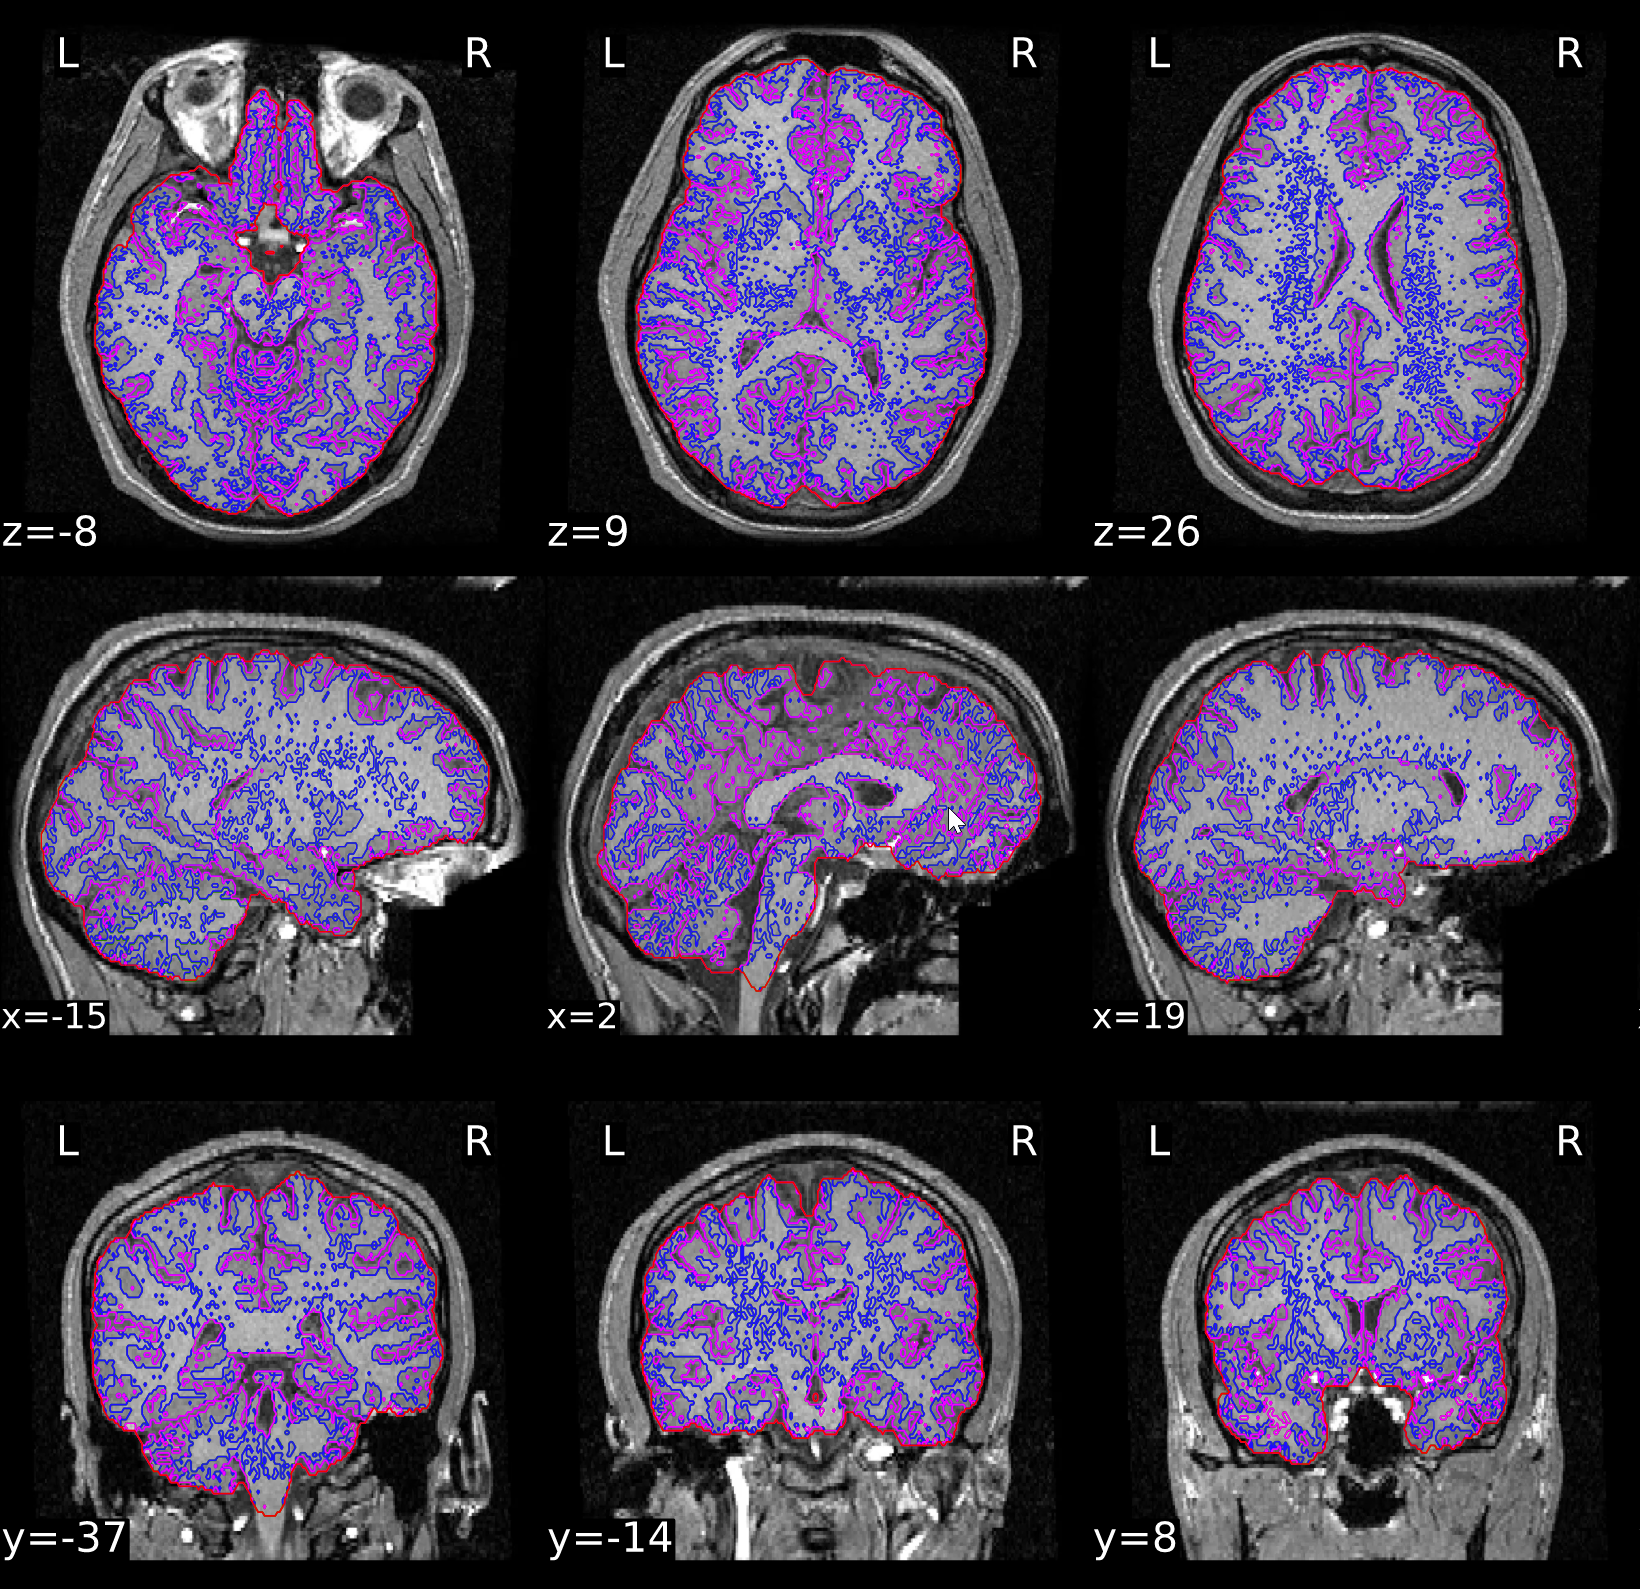

ds000119/reportlets/fmriprep/sub-26/anat/sub-26_T1w_seg_brainmask.svg